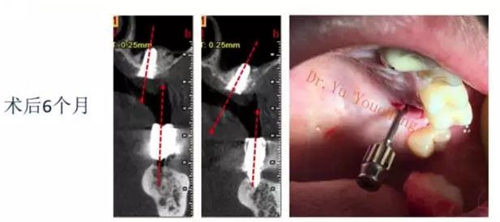

系列課開播前小編為大家預(yù)告了一例上頜竇外提升術(shù)后種植體方向改變的病例,當(dāng)時頓生種種疑惑:“真的么?怎么會?怎么辦!!”在本次課程中余教授給出了答案:上頜竇外提升同期種植有一重要的因素,即種植體初期穩(wěn)定性的獲得。該患者由于其骨量的嚴(yán)重不足,雖然可通過大直徑覆蓋螺絲保證種植體不至于滑落,但隨著竇粘膜的運(yùn)動和部分移植骨的吸收,種植體方向最終受到了影響,這也提示我們在制定治療計劃過程中應(yīng)慎重考慮這一因素,以確保更好的種植預(yù)后效果。